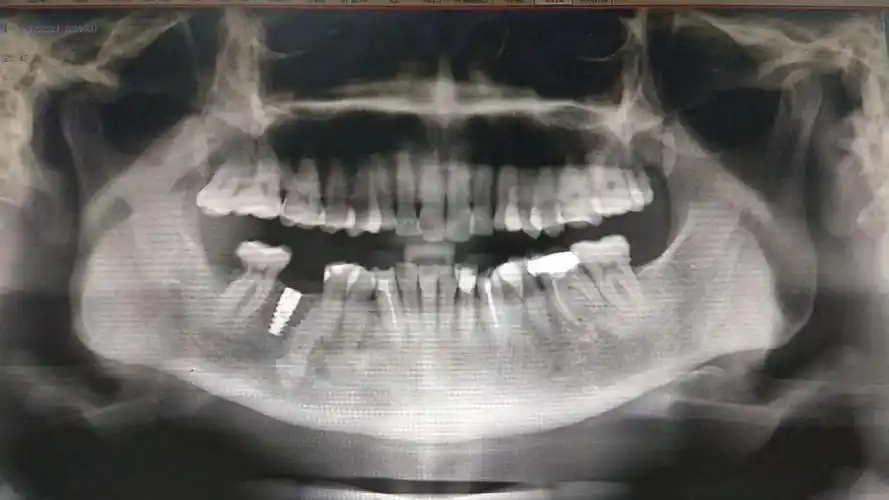

种植牙术前术后拍片对比

吴女士种植带冠后的牙片显示,种植体就位精准,受力均衡

青年牙医胡医生种植牙病例分享

我的种植牙日记机械维修工程师的渡江口腔种植修复之路